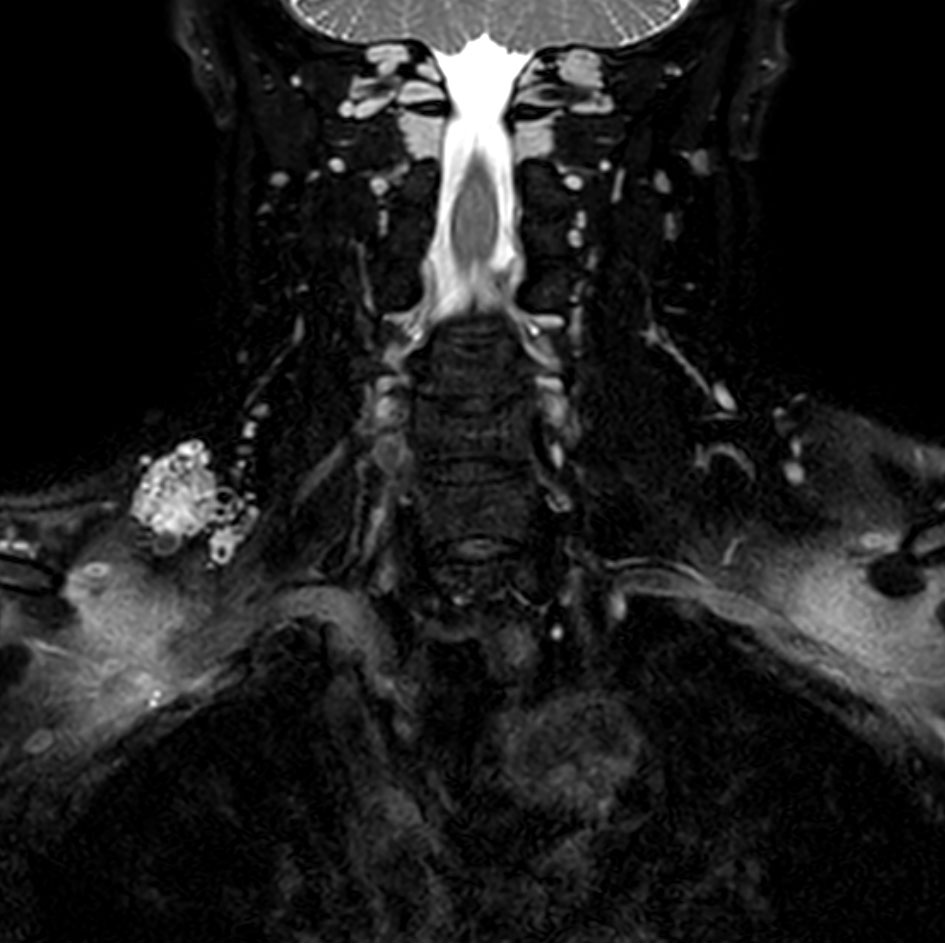

Coronal T2w mDIXON XD TSE (In Phase)

Coronal T2w mDIXON XD TSE (Water only)

Coronal T2w VISTA